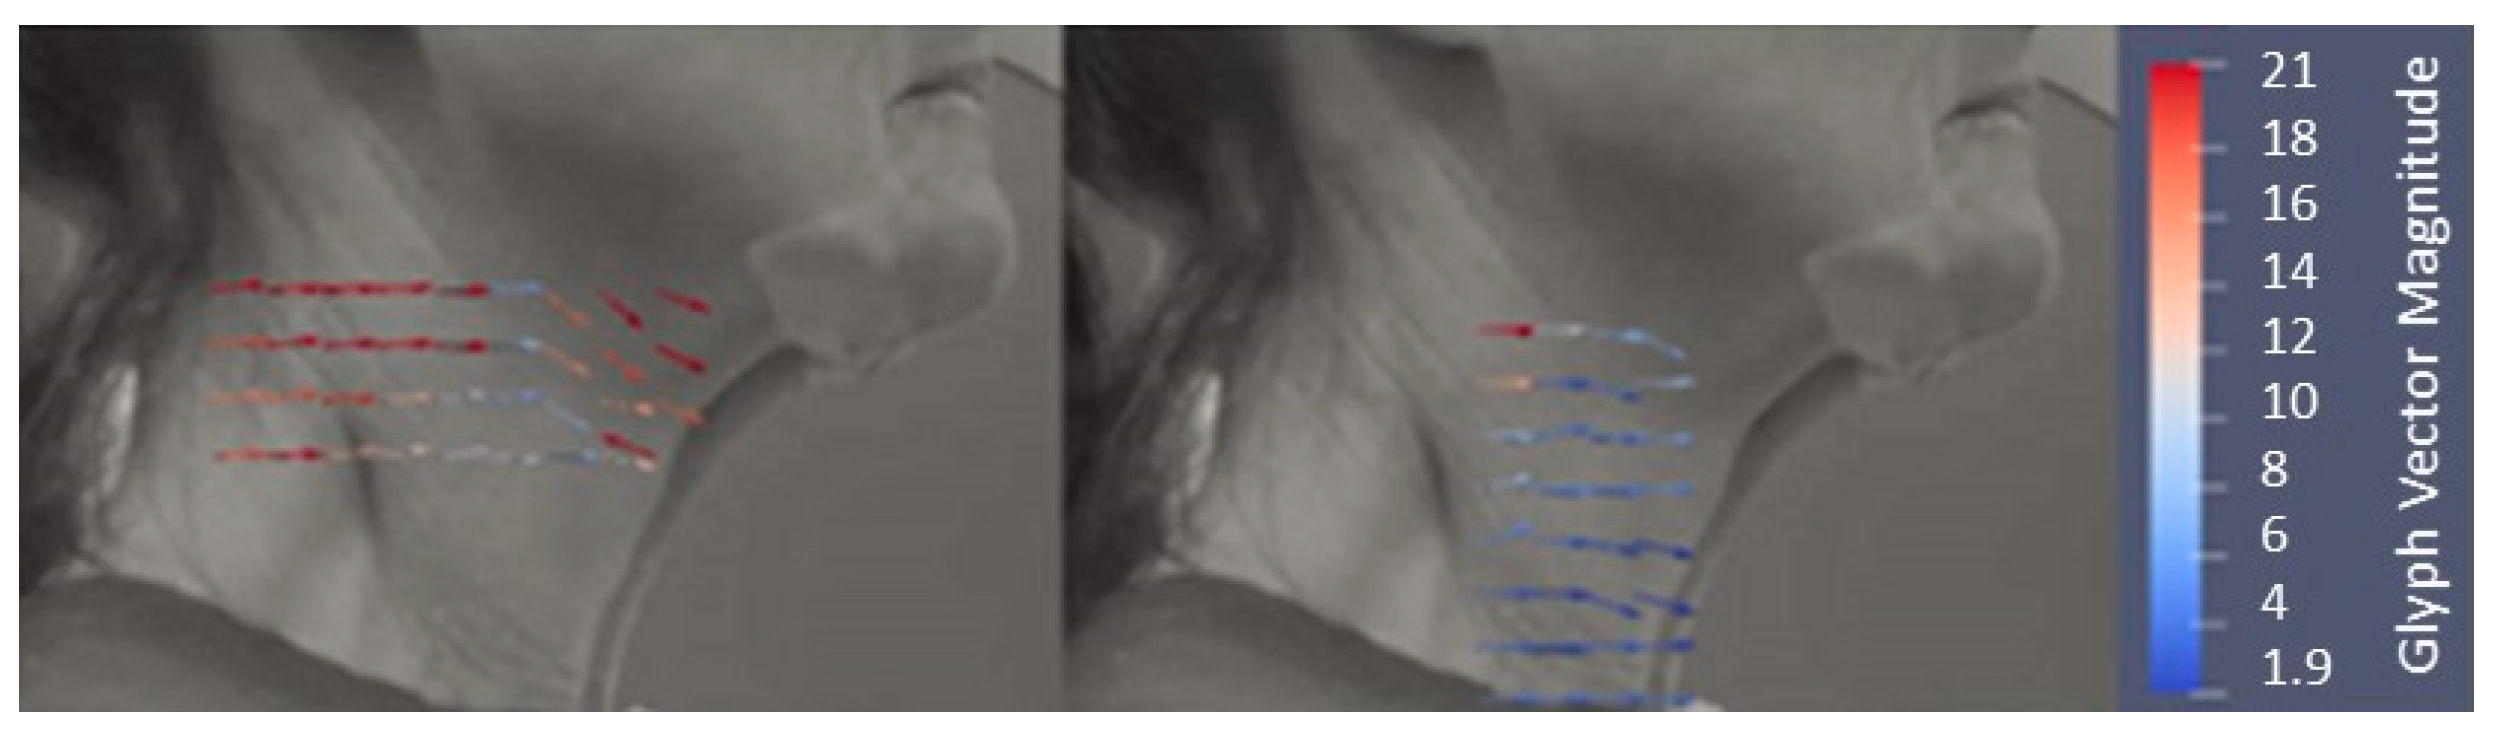

2.5. Skin Displacements